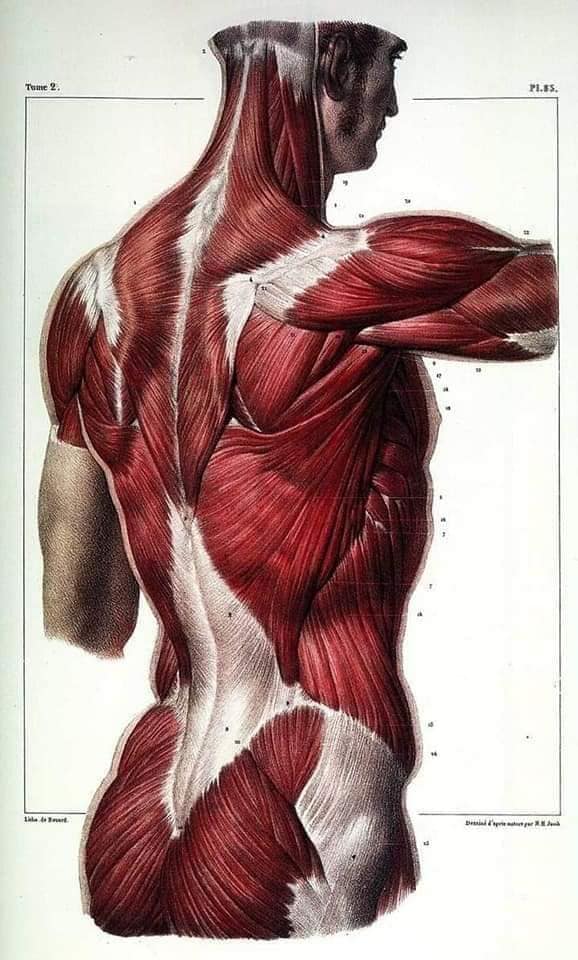

Спинні м'язи

Спинні м'язи виконують функції підтримки хребта, а також дозволяють здійснювати рухи тулуба.

Поверхневі спинні м'язи

М'язи, що піднімають лопатку: Трапецієподібний м'яз: великий м'яз, що покриває верхню частину спини. Його функція - підтримка і рух лопаток, а також забезпечення стабільності хребта.

М'язи, що ведуть лопатку до хребта: Широкий м'яз спини: великий м'яз, що розташований в нижній частині спини. Він відповідає за рухи плечей і лопаток, а також за розширення верхньої частини тулуба.

Глибинні спинні м'язи

М'язи, що забезпечують стабільність хребта: М'язи, що розташовані між хребцями: включають мускулатуру, яка забезпечує стабільність і підтримку хребта, а також дозволяє здійснювати рухи хребта.